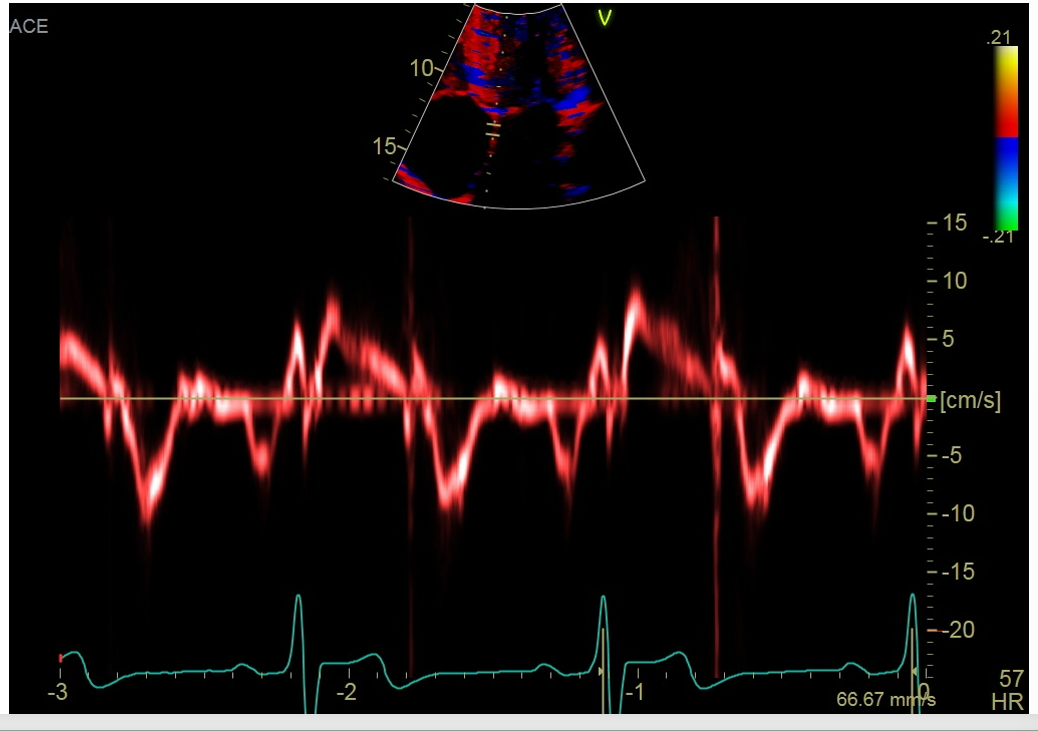

what is this measurement for

Septal side

measure the MV septal E

and then MV septal A velocity

gate should be 5-10

what measurement is this for

Lateral side

Peak lateral e’ and a’